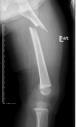

桡骨陈旧性骨折骨不连、畸形

先天性胫骨假关节

肢体短缩延长术,延长9厘米

术前 手术 术后功能恢复良好